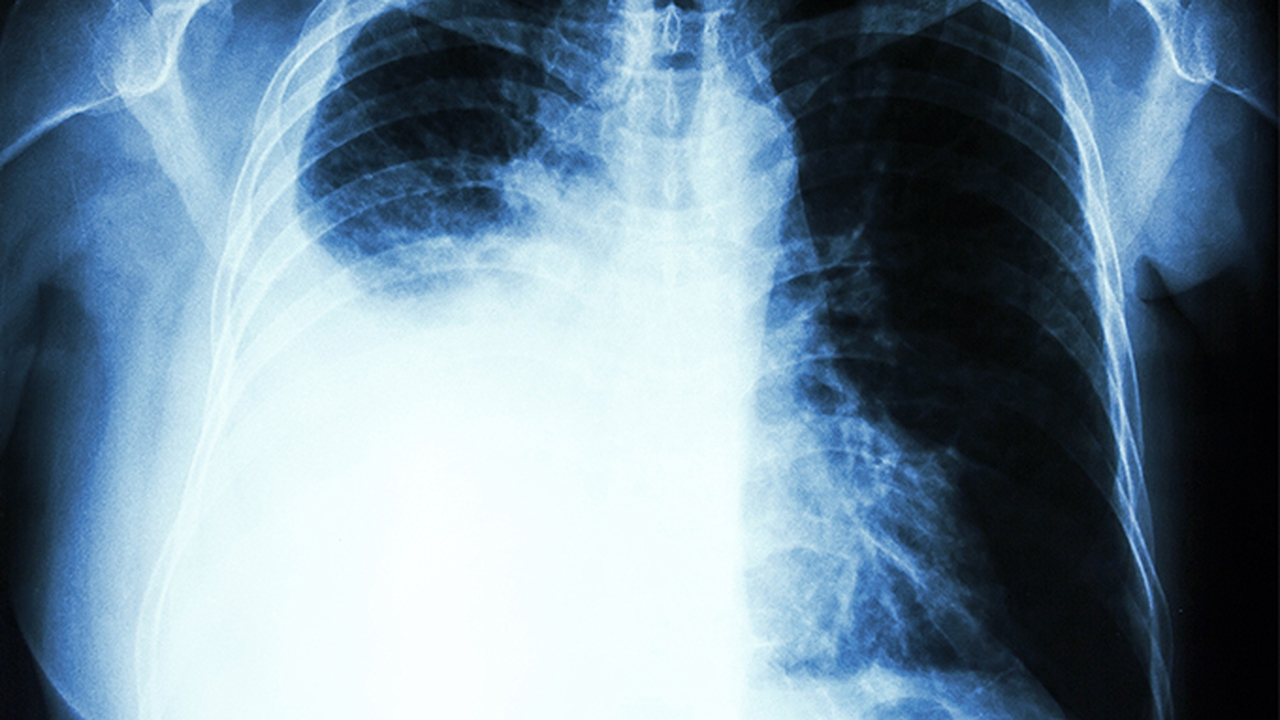

血氧饱和度低于90%时需进行鼻导管吸氧,氧流量控制在2-4升/分钟。严重低氧血症患者可能需使用无创呼吸机辅助通气,治疗期间需定期监测动脉血气分析指标。

患者应保持低盐高蛋白饮食,适量补充维生素C和维生素D增强免疫力。恢复期可进行腹式呼吸训练改善肺功能,运动强度以不引起气促为度。建议每3个月复查胸部CT评估病情进展,气候变化时注意佩戴口罩避免冷空气刺激。出现痰中带血、持续胸痛等症状需立即就医。